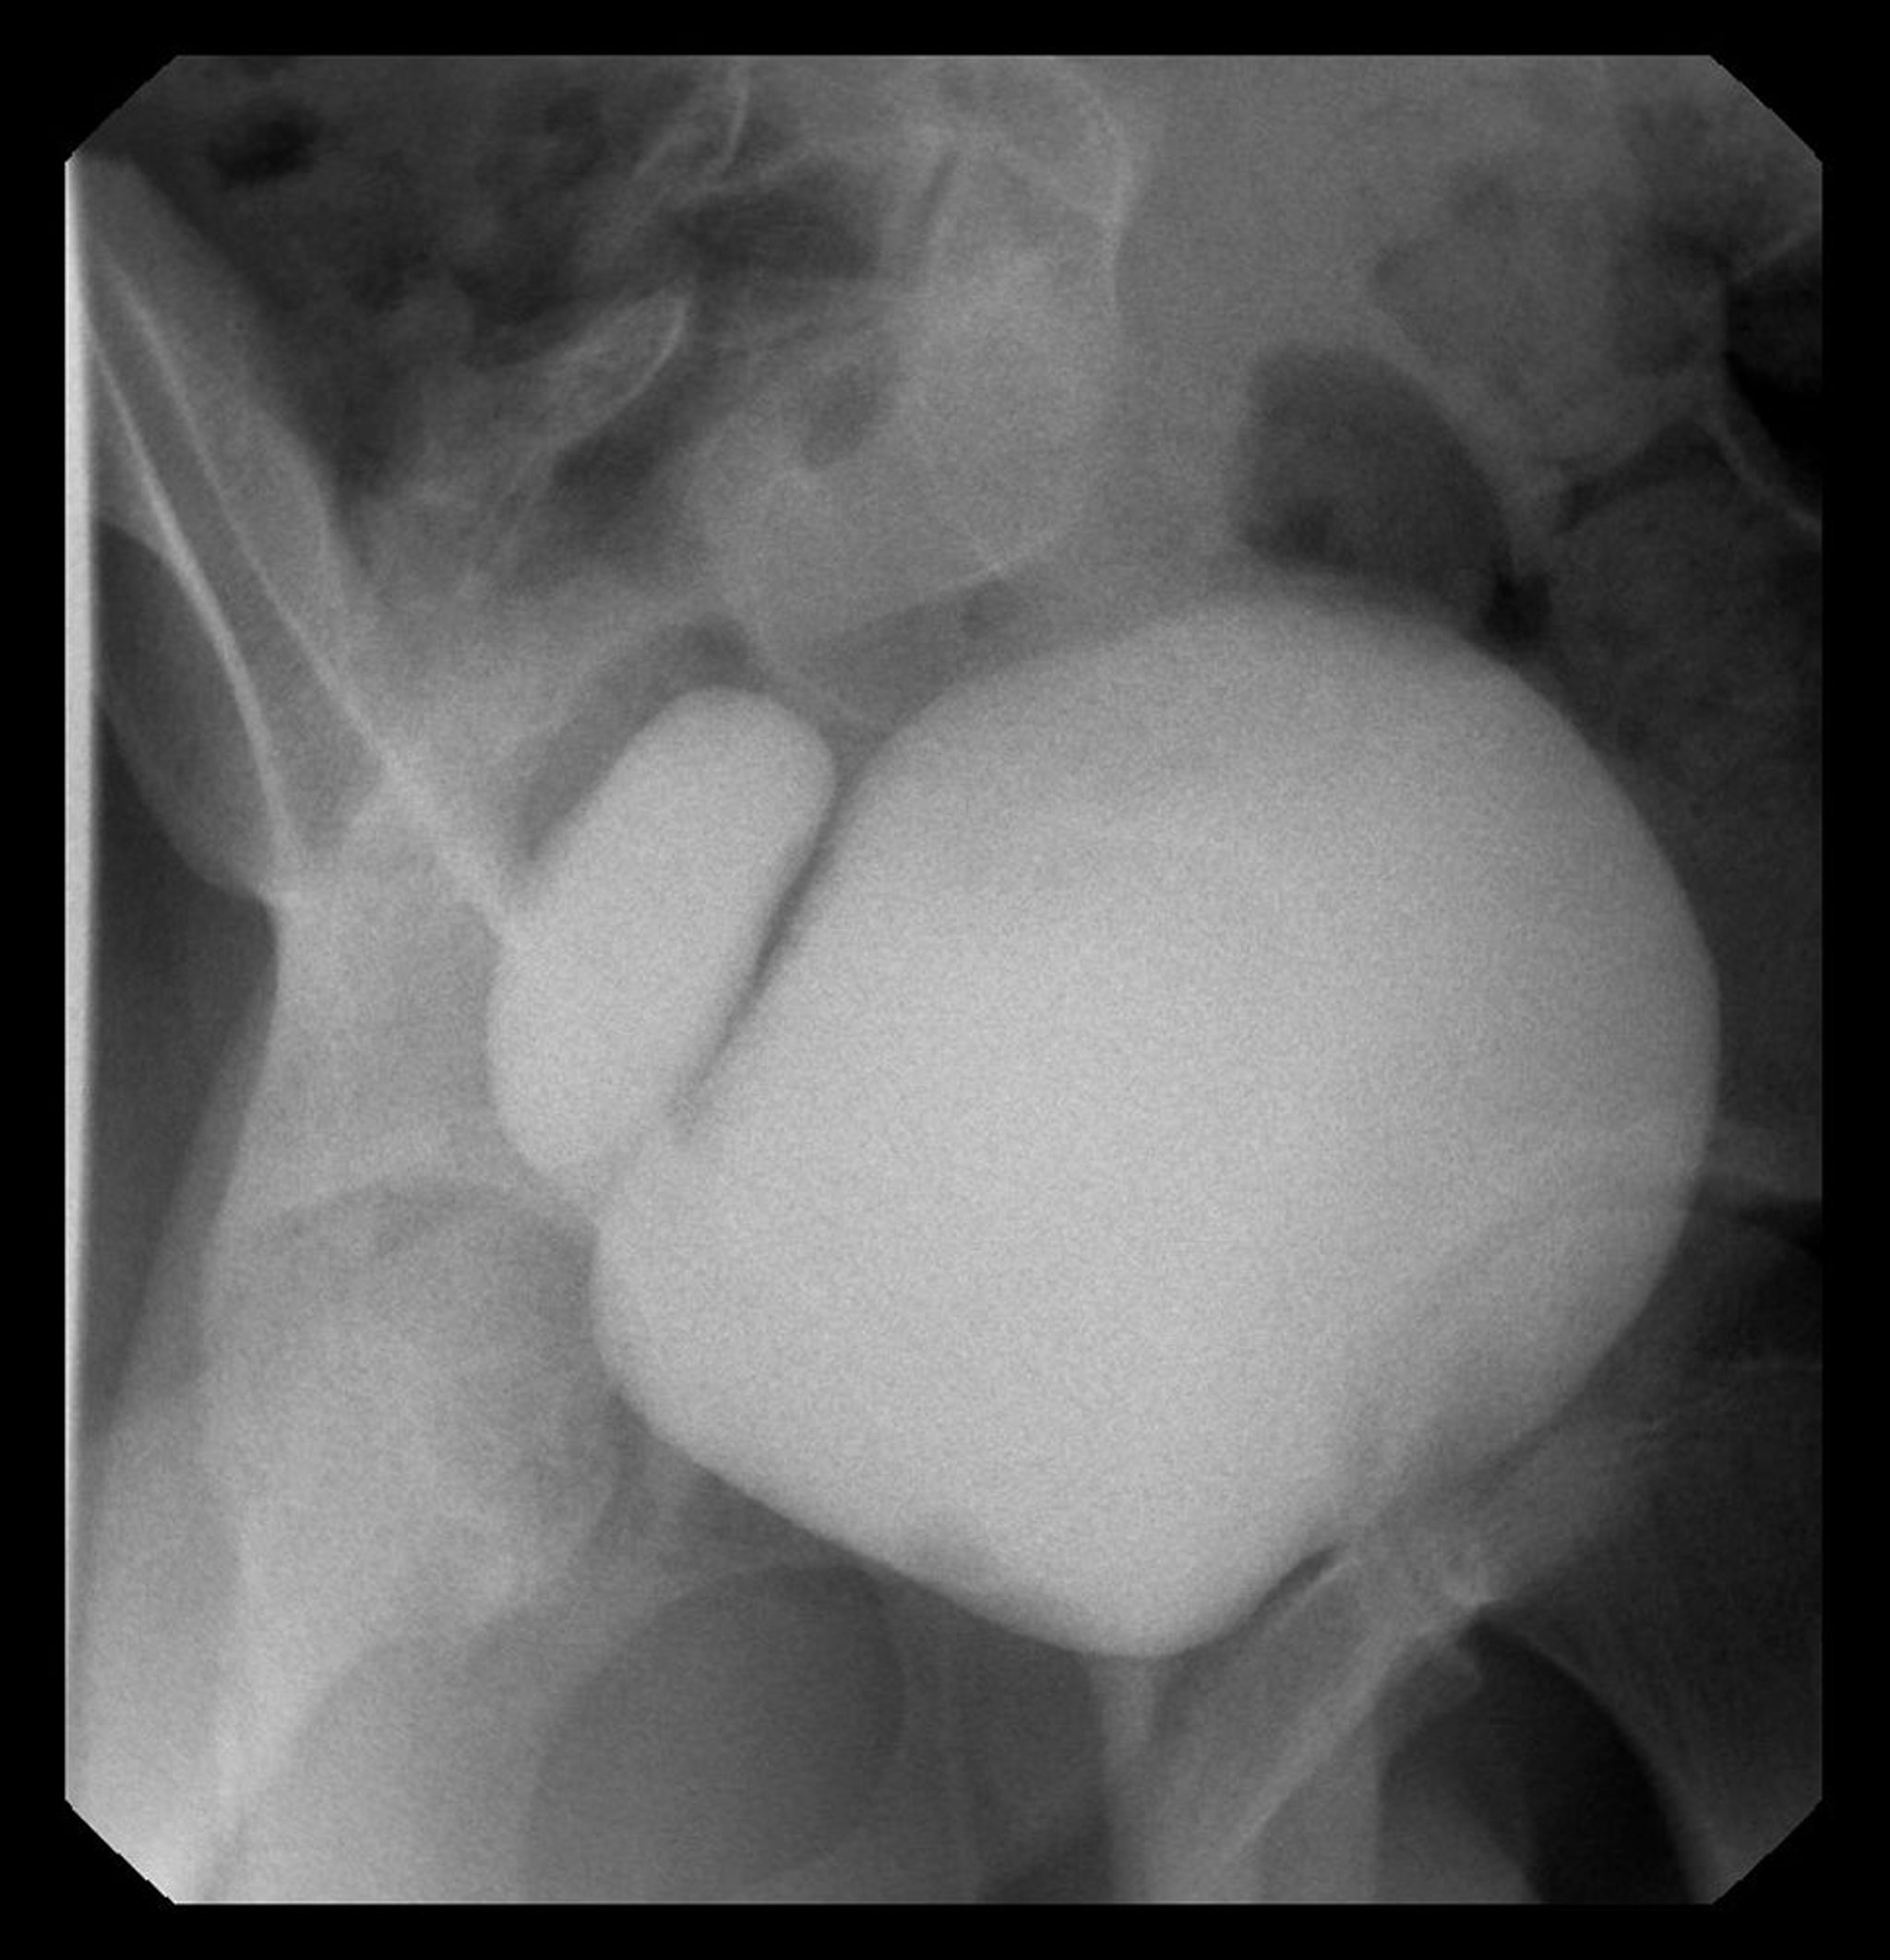

Esta imagen muestra un cistograma con divertículo vesical derecho.

Image courtesy of Drs. Ronald Rabinowitz y Jimena Cubillos.